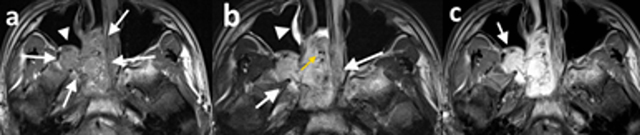

Figure 3

15-year-old male patient (patient 1), (a) axial T1-weighted precontrast, (b) axial T2-weighted precontrast, and (c) axial T1-weighted postcontrast MR images demonstrate a right-sided nasopharyngeal mass which enlarges the ipsilateral pterygopalatine fossa (a and b white arrows). The mass is isointense with the muscle on T1-weighted image (a) and hyperintense on T2-weighted image (b) and exhibits significant contrast enhancement (c). The posterior wall of the maxillary sinus demonstrates anterior bowing with resultant Holmann Miller sign (a, white arrowhead; c, arrow). The tumor demonstrates signal-void regions (b, yellow arrow) and inflammatory signal changes in maxillary sinuses (b, white arrowhead).